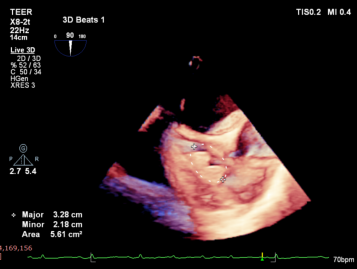

Annuloplasty Outcome:

Summary

The K-Clip® transcatheter tricuspid valve annuloplasty adopts a unique physiological annuloplasty technology with no damage to native valve leaflets. Even in the face of complex anatomical structures such as myxomatous degeneration of tricuspid valve leaflets, mild prolapse of the valve body and mild balloon-like changes, this technology can still accurately reduce the annulus and complete annulus remodeling.